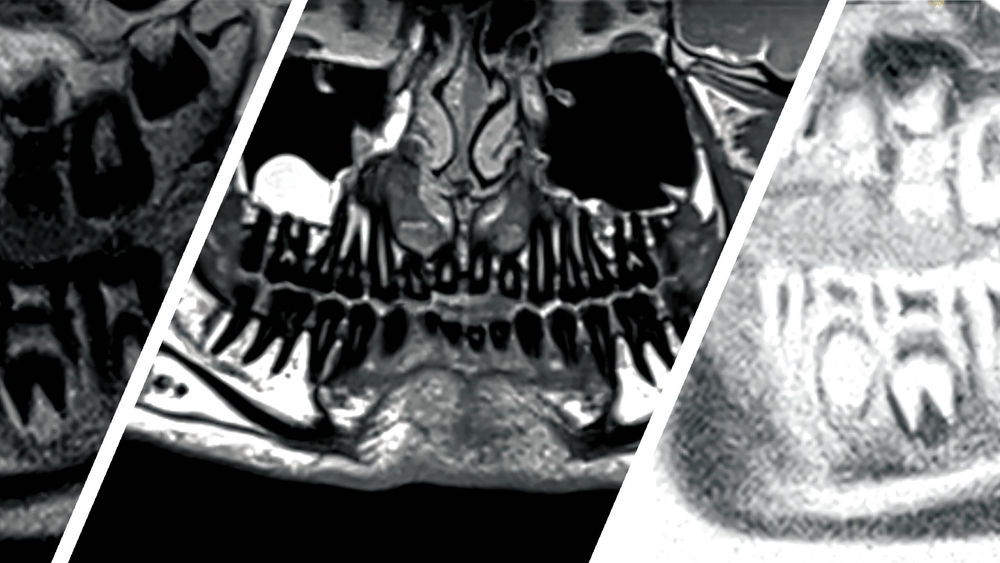

Ein achtjähriger Patient stellte sich mit einer tastbaren Raumforderung regio 36 vestibulär und intermittierenden Schmerzen vor. Während im Röntgen nur unspezifische periapikale Strukturveränderungen zu sehen waren, zeigte das MRT gut sichtbar eine entzündliche Läsion, vereinbar mit einem intraossären Abszess. Differenzialdiagnostisch konnten ein Hämangiom oder ein Tumor ausgeschlossen werden. Postoperativ konnten dank der strahlenfreien Bildgebung Verlaufsaufnahmen angefertigt werden – so ließ sich ein Rezidiv ausschließen.

Abb. 1: Panoramaschichtaufnahme mit kaum sichtbarer Läsion mit unspezifischer periapikaler Strukturveränderung an Zahn 36 im altersentsprechenden Wechselgebiss

Abb 2: Koronares MRT-Bild (inflammation_3d) durch die Mitte der Läsion, 1 = Zahn 36, 2 = Läsion: Gut sichtbar ist die Ausdehnung der entzündlichen Läsion von der Unterkieferbasis bis zur Bifurkation des Zahnes 36.

Abb. 3: Verlaufskontrolle mit Panorama-Rekonstruktion acht Wochen postoperativ auf Basis der Anatomie-3D-Sequenz mit 0,5 mm Schichtdicke und 1 mm Abstand zwischen den Schichten, 1 = mesiale Wurzel des Zahnes 36, 2 = restliches Granulationsgewebe nach Abheilung